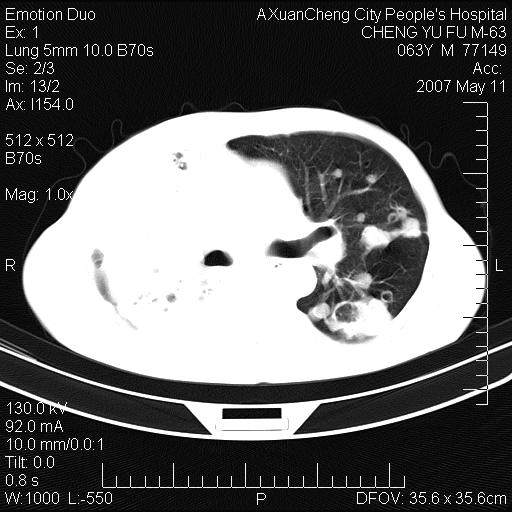

以下是引用小初学者在2007-5-11 19:32:00的发言:[br]1、首先考虑干酪性肺炎支气管播散[br]2、支气管肺泡癌待排

以下是引用zhangzhongshou在2007-5-11 19:30:00的发言:[br]细支气管肺泡癌可能性大。